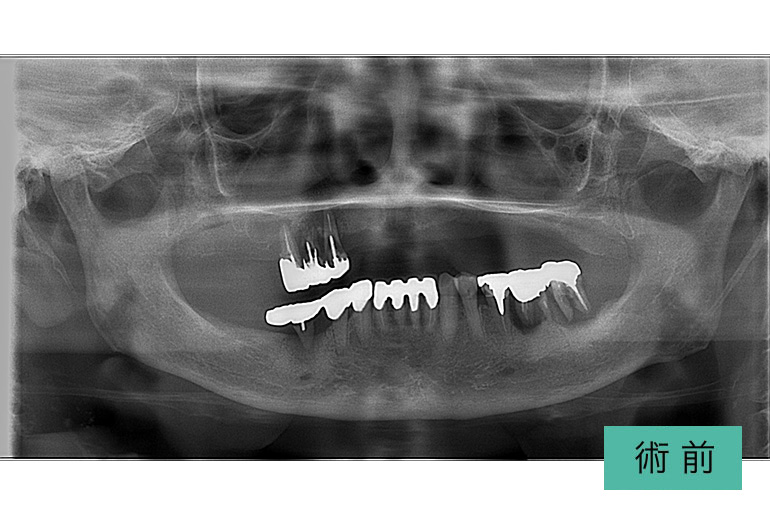

上顎総インプラント

| 治療内容 | 両側サイナスリフト(上顎洞底挙上骨造成術)し、上顎総インプラント治療を行った |

|---|---|

| 治療期間・回数 | 1年9ヶ月、29回(他部位の治療を含む) |

| 費用(税込) | ¥4,935,000 ※自由診療 |

| リスク・副作用 | 疼痛、腫脹、出血、鼻血、青痣、補綴の脱落、インプラント周囲炎、神経麻痺 |